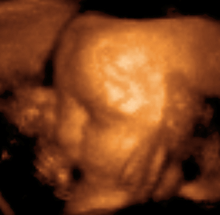

Medical sonography (ultrasonography) is an ultrasound-based diagnostic medical imaging technique used to visualize muscles, tendons, and many internal organs, to capture their size, structure and any pathological lesions with real time tomographic images. Ultrasound has been used by radiologists and sonographers to image the human body for at least 50 years and has become a widely used diagnostic tool. The technology is relatively inexpensive and portable, especially when compared with other techniques, such as magnetic resonance imaging (MRI) and computed tomography (CT). Ultrasound is also used to visualize fetuses during routine and emergency prenatal care. Such diagnostic applications used during pregnancy are referred to as obstetric sonography. As currently applied in the medical field, properly performed ultrasound poses no known risks to the patient.[23] Sonography does not use ionizing radiation, and the power levels used for imaging are too low to cause adverse heating or pressure effects in tissue. Although the long-term effects due to ultrasound exposure at diagnostic intensity are still unknown,[24] currently most doctors feel that the benefits to patients outweigh the risks.[25] The ALARA (As Low As Reasonably Achievable) principle has been advocated for an ultrasound examination – that is, keeping the scanning time and power settings as low as possible but consistent with diagnostic imaging – and that by that principle non-medical uses, which by definition are not necessary, are actively discouraged.[26]